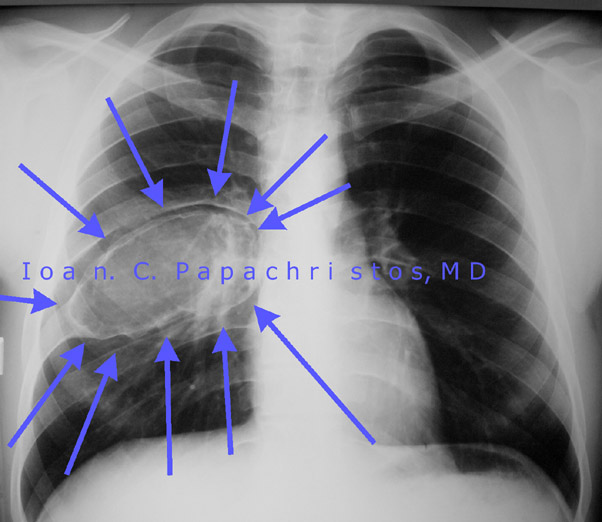

Preop CXR of the rib's Giant Aneurysmal Cyst